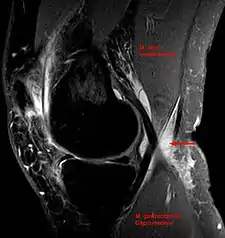

In adults, Baker's cysts usually arise from almost any form of knee arthritis (e.g., rheumatoid arthritis) or cartilage (particularly a meniscus) tear. Baker's cysts in children do not point to underlying joint disease. Baker's cysts arise between the tendons of the medial head of the gastrocnemius and the semimembranosus muscles. They are posterior to the medial femoral condyle.

The synovial sac of the knee joint can, under certain circumstances, produce a posterior bulge, into the popliteal space, the space behind the knee. When this bulge becomes large enough, it becomes palpable and cystic. Most Baker's cysts maintain this direct communication with the synovial cavity of the knee, but sometimes, the new cyst pinches off. A Baker's cyst can rupture and produce acute pain behind the knee and in the calf and swelling of the calf muscles.

Baker's cyst on axial MRI with communicating channel between the semimembranosus muscle and the medial head of the gastrocnemius muscle.